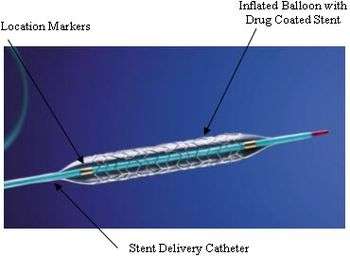

| Coronary stents are placed during a percutaneous coronary intervention, also known as angioplasty. The most common use for coronary stents is in the coronary arteries, into which a bare-metal stent, a drug-eluting stent, a bioabsorbable stent, a dual-therapy stent (combination of both drug and bioengineered stent), or occasionally a covered stent is inserted. |  A coronary stent |